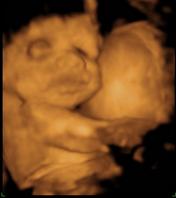

Csinált uh-t? Mikor mész legközelebb? Nem mérte meg Nimócit mekkora? Te mész 4D-re?